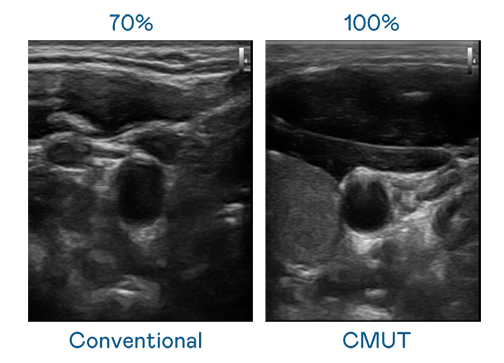

CMUT 技术是一种用电容式微机电元件来产生超音波讯号的技术。与传统 PZT 压电式技术相比,CMUT 频宽增加 30%,更宽频的超音波讯号让影像解析度大幅提升,是实现高影像品质医疗超音波扫描、促进精准医疗发展的关键技术。

超音波影像的解析度高低,首先取决于探头能发出的讯号频宽。永利皇宫官网 CMUT 可提供高清晰的超音波讯号,提供高频宽、高灵敏度、影像纹理细节更高的超音波影像,协助医护人员缩短影像判读时间及利用精准的医疗影像进行诊断。